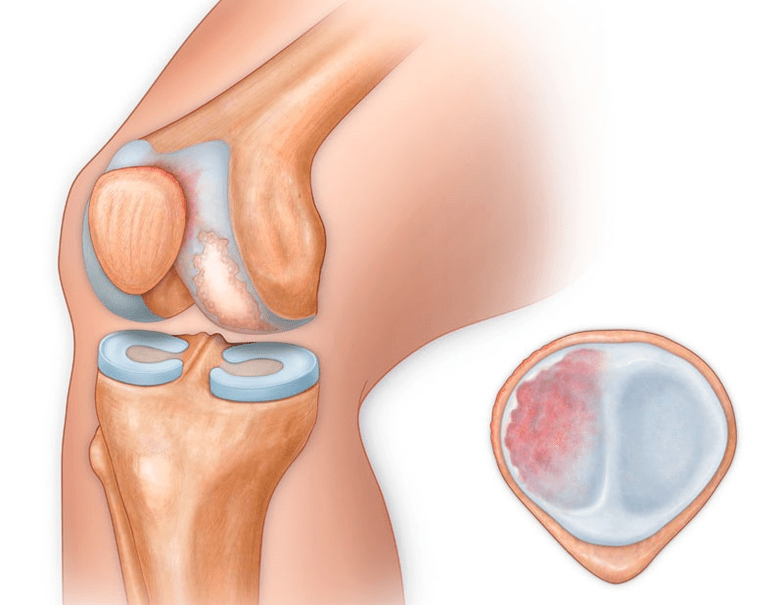

In addition to the inner or outer part of the knee, arthrosis can also affect the surfaces between the patella and the intercondylar groove of the femur.This option is calledpatellofemoral arthrosis.

Its cause is usually a subluxation, fracture, or lateralization of the patella.

At the second stage, the cartilage layer becomes sharply thinner, and in some places is completely absent.Osteophytes appear along the edges of the articular surfaces.The qualitative and quantitative characteristics of the synovial fluid of the joint change - it becomes thicker, more viscous, which leads to a deterioration in its nutritional and lubricating properties.The pain is more prolonged and intense, and a crunching sound often appears when moving.There is a slight or moderate restriction of movement and slight deformation of the joint.Taking analgesics helps relieve pain.

Lack of cartilage in most affected areas, severe sclerosis (hardening) of the bone, many osteophytes and a sharp narrowing or absence of the joint space.The pain is almost constant, gait is impaired.Mobility is sharply limited, and joint deformation is noticeable.NSAIDs, physiotherapy and other standard methods of treating knee arthrosis are ineffective.